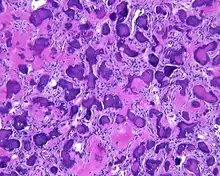

By microscopic evaluation, the tumors are composed of a variably cellular stroma make up of spindled to stellate fibroblast-like cells. Within this stroma, are numerous small, rounded, mineralized collagenous ossicles and immature osteoid. Many times the curved-shaped bone fragments have a collagenous rim around them. Ossicles may fuse to form much large mineralizations. Cementum-like psammomatous bodies (cementicles) may also be present. Osteoblastic rimming is not uncommon. Occasionally, giant cells and even mitoses are seen.[1][3]